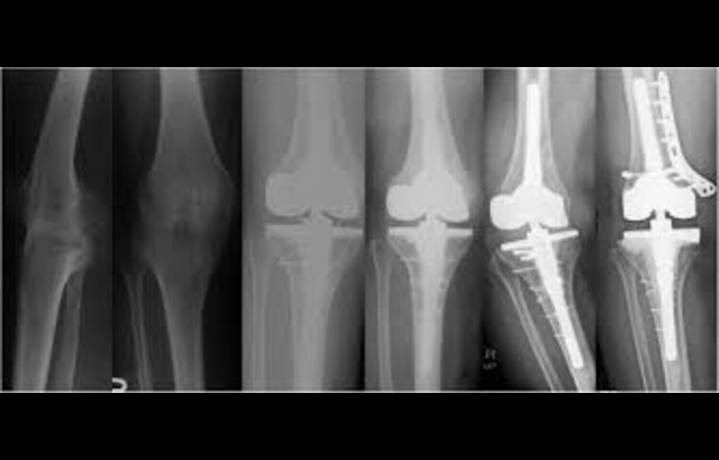

Total knee arthroplasty (TKA) is widely used to treat end-stage knee disorders, but its role in ankylosed knees has long been debated due to the technical complexity and heightened risk of complications. A recent study has provided important insights, showing that although patients with ankylosed knees experience lower recovery of range of motion (ROM) and face higher complication rates compared with conventional osteoarthritis cases, Total knee arthroplasty still delivers meaningful improvements in function, mobility, and quality of life.

In this retrospective analysis, researchers evaluated outcomes of patients with ankylosed knees who underwent Total knee arthroplasty. Preoperatively, most patients had severely restricted or no motion, limiting independence and quality of life. After s